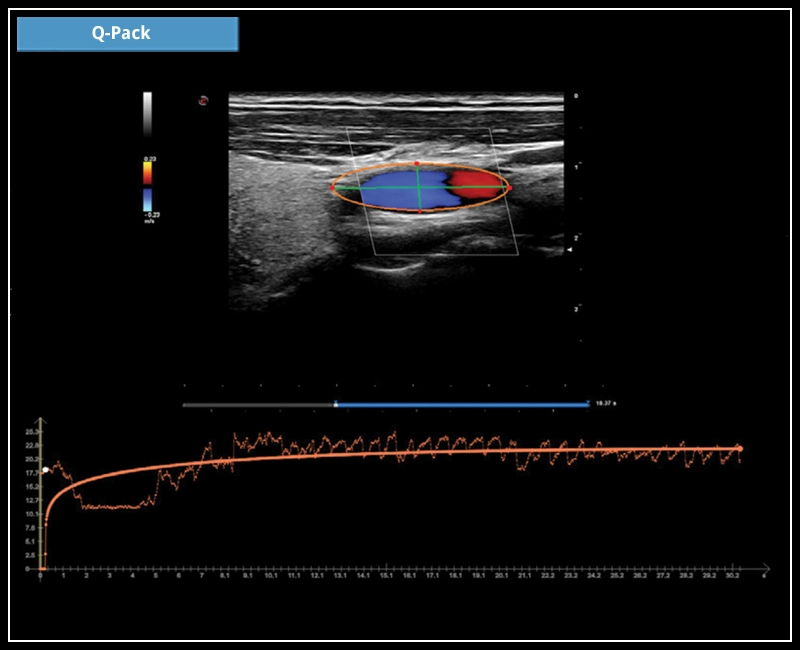

MyLab™X7 - Q-Pack

MyLab™X7 - Q-Pack